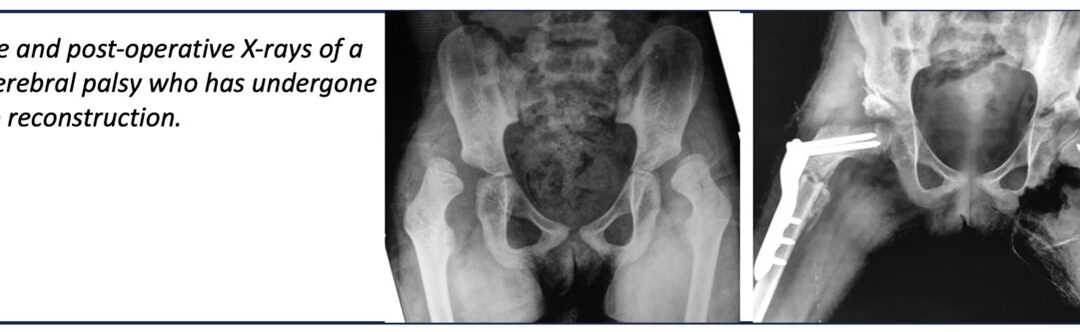

Introduction: Cerebral palsy (CP) also called “static encephalopathy” affects movement, posture, and muscle coordination. It is caused by damage to the developing brain during pregnancy, childbirth, or shortly after birth. One of the most common orthopaedic issues...